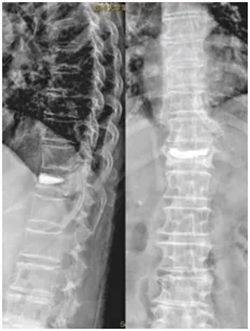

▲ 术后X线

现在常用的是微创骨水泥手术,刘老太就是接受了这种治疗。骨科一病区科主任徐明杰和张鹏飞主治医生往她骨折的椎体里注入了一种叫“骨水泥”的材料,凝固后就能把压扁的骨头撑起来,快速稳定脊柱、缓解疼痛。

这种手术伤口很小,恢复也快,大多数患者术后一两天就能下床活动,腰痛能明显缓解。